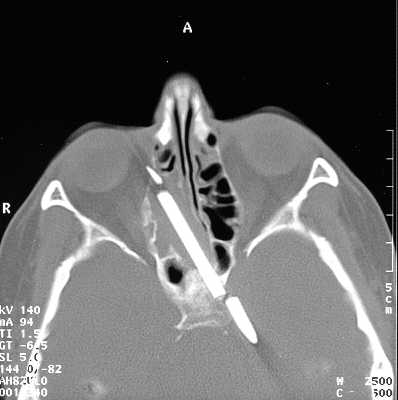

6厘米铅笔从大脑里取出来了